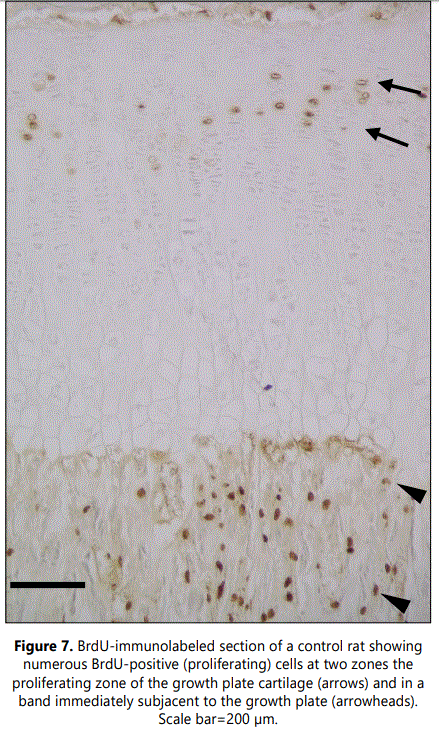

Examination of cell proliferation, assessed by BrdU incorporation, demonstrated two zones with high numbers of BrdUrd-positive cells (Figure 7). One corresponded to the region of the growth plate cartilage where chondrocytes undergo mitosis, the proliferating zone. The second was within the metaphyseal primary spongiosa, in a band immediately subjacent to the growth plate, and corresponded to osteoprogenitor cells capable of both proliferating and differentiating into bone-forming osteoblasts. Analysis of sections from clodronate treated rats revealed that the number of BrdUrd-positive chondrocytes in the growth plate cartilage did not change when compared with control rats. However, proliferation was found to be significantly decreased in the primary spongiosa of clodronate treated rats (Figure 8) (Table 1). Proliferating cells in the primary spongiosa included mesenchymal, osteoprogenitor, hematopoietic and vascular cells. Some of these cells migrate with the invading blood vessels into the hypertrophic cartilage and others generate osteoblasts that generate bone trabeculae at the primary spongiosa. Results obtained on the structure of growth plate and primary spongiosa showed that alteration was greater in the last than in the former, a fact suggesting that decrease of proliferating cells mainly affected to osteoprogenitor cells.

Two zones with high proliferative activity were found associated with the growth plate. One is the proliferating zone of the growth plate cartilage and the other is a zone of the metaphyseal primary spongiosa, immediately subjacent to the growth plate, where osteoprogenitor cells proliferate to subsequently differentiate into bone-forming osteoblasts. Results obtained in the present work showed that clodronate treatment does not alter the proliferation of chondrocytes but significantly decreases proliferation in the primary spongiosa. This reduction in cell proliferation may be a result of the reduction of osteoclastic activity because it has been demonstrated that growth factors like insulin-like growth factor type 1 (IGF-1) and transforming growth factor-beta (TGF-β) are released from the bone matrix due to osteoclast matrix resorption and such factors induce proliferation and differentiation of mesenchymal stem cells into osteoblasts [30-32]. Furthermore, osteoclasts may promote osteogenesis independent of resorptive activity since they produce secrete diverse signaling molecules, like platelet-derived growth factor, that induce recruitment of endothelial precursor cells and mesenchymal stem cells for angiogenesis and osteogenesis [33-35]. On this basis, the decreased proliferation activity in the primary spongiosa reported in the present work may be a consequence of a modification in cell signaling due to the alteration of osteoclatic number and/or activity.